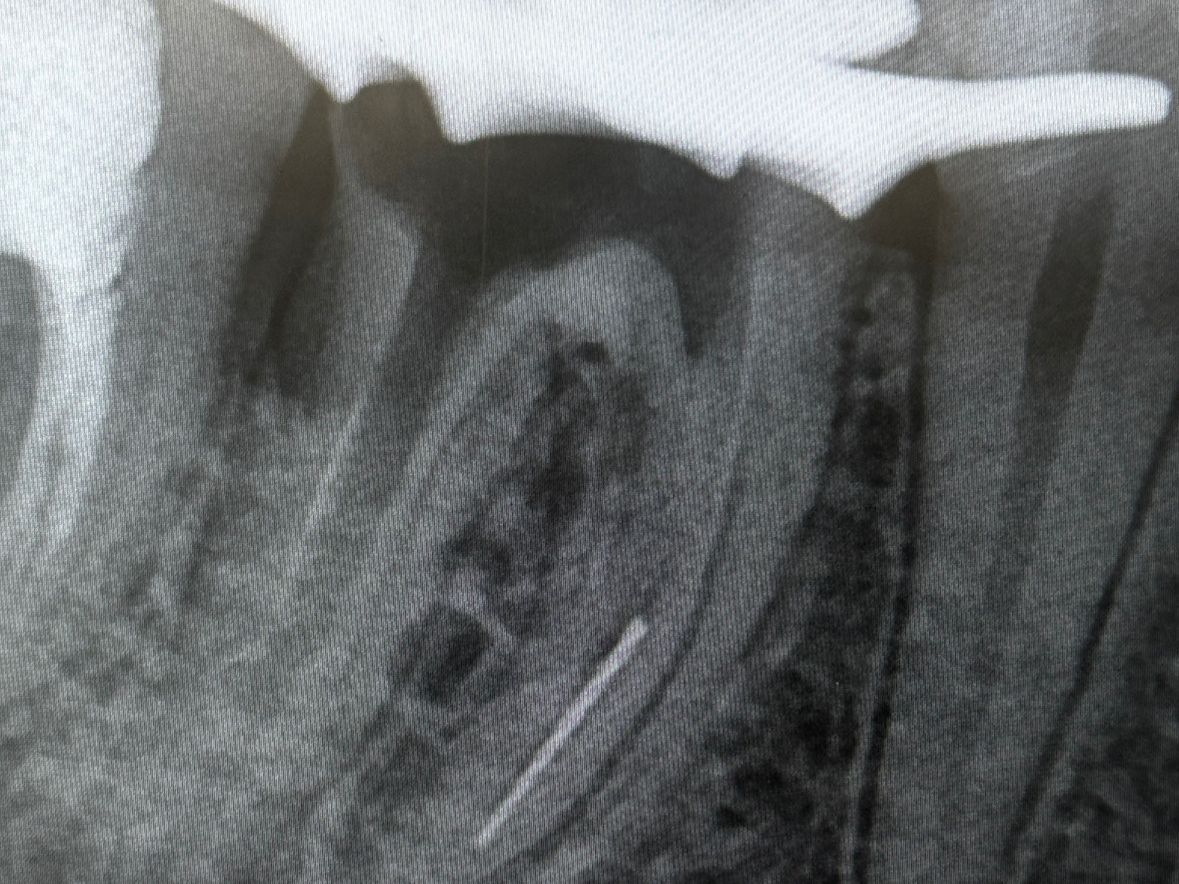

• Лечением кариозных поражений всех стадий, а также их осложнений, таких как пульпиты и периодонтиты.

• Восстановлением разрушенных зубов с последующей подготовкой их под ортопедические конструкции.